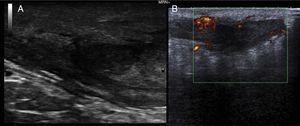

Un varón de 51 años, fumador y con antecedentes personales de diabetes mellitus tipo 2. Fue derivado al servicio de dermatología por un nódulo doloroso y supurativo inguinal izquierdo de un año de evolución resistente a múltiples tratamientos antibióticos prescritos por el médico de atención primaria. El examen físico mostró una lesión subcutánea eritematosa con áreas de supuración en zona inguinal inferior izquierda que se extendía a la palpación hacia la zona perineal (fig. 1). Además, asociaba 3 lesiones clínicamente compatibles con condilomas acuminados en la región perianal. Con el diagnóstico clínico de hidradenitis supurativa (HS) se realizó una ecografía con sonda lineal de 18MHz que demostró la presencia de un tracto fistuloso, con áreas de colección líquida, junto a una vascularización intensa en el doppler (fig. 2). Dada la localización y profundidad de la lesión, el paciente fue remitido a la consulta de proctología del área de cirugía para la extirpación completa de la lesión. El examen histológico mostró cambios compatibles con HS y un carcinoma escamocelular (CEC) bien diferenciado sobre el trayecto fistuloso que se encontraba cercano al límite profundo de resección. No se observó invasión vascular ni infiltración perineural (figs. 3A y B). Se decidió ampliar los márgenes quirúrgicos sin encontrarse evidencia de neoplasia residual, pero con presencia de focos sugestivos de infección viral (fig. 3C). La tinción inmunohistoquímica con p16 fue intensamente positiva (fig. 3D). Se investigó la presencia del virus del papiloma humano (VPH) mediante PCR y genotipado por hibridación in situ sobre microarrays de tejido incluido en parafina, siendo el resultado positivo a genotipo 6 (considerado de bajo riesgo), el cual se demostró también en los condilomas acuminados perianales. Se realizó analítica con serología hepática y VIH negativas. Después de 12 meses de seguimiento clínico y de imagen (TAC y RMN pélvica), el paciente no muestra signos de recidiva local ni de metástasis.

Tanto la ecografía como la RMN pueden ser muy útiles en el establecimiento de la verdadera extensión anatómica de la enfermedad antes del tratamiento quirúrgico10. La extirpación amplia de la lesión se considera el tratamiento estándar. El CEC que surge en áreas de inflamación crónica debido a la HS es frecuentemente de tipo bien diferenciado. No obstante, a pesar de este teórico buen pronóstico histológico se puede observar un rápido crecimiento, agresividad local, metástasis tempranas y elevada mortalidad1.